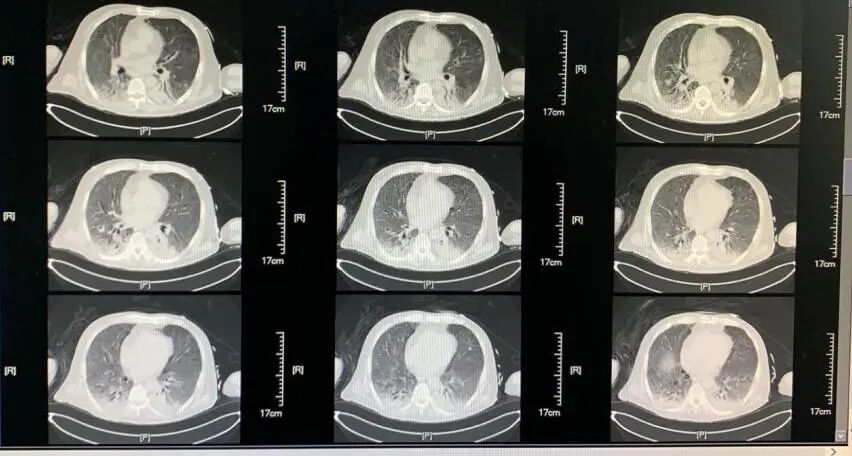

这是一个62岁的男性患者,主因「发热伴呼吸困难1月余」入院,否认其他慢性疾病病史。起病前1周左右,该患者与家人共同进餐,家人后证实为COVID-19确诊病例。患者入院前1月余无明显诱因出现发热,伴乏力,否认其他伴随症状。4天后出现胸闷,伴呼吸困难。于当地医院查鼻咽拭子SARS-nCoV-2核酸阳性,确诊COVID-19后接受抗病毒(盐酸阿比多尔)、糖皮质激素抗炎(甲强龙40mg bid*7d)、免疫调节(丙种球蛋白20g qd*10d,胸腺肽1.6mg qod)及输注2019-nCoV灭活血浆等对症支持治疗后,呼吸困难症状仍进行性加重,I型呼吸衰竭需有创机械通气支持,辅助检查主要表现为淋巴细胞计数持续低下(160-500cell/uL左右),影像学表现为双肺弥漫磨玻璃改变伴双下肺实变(图1)。此外,当地医院治疗约3周左右出现体温再次升高,气道内出现黄色脓性分泌物,白细胞计数显著升高,经「美罗培南、替加环素、伏立康唑」等抗菌药物治疗后,病情无明显改善,为求进一步治疗转入我病区。

【图1】(2020-02-26胸部CT)